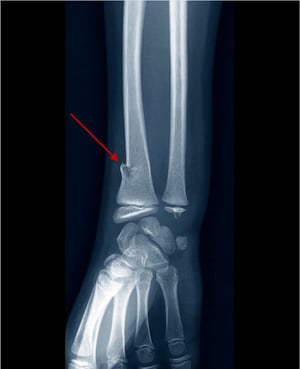

Перелом дистального відділу променевої кістки по типу «зеленої гілки»

На даній рентгенограмі показаний перелом по типу «зеленої гілки», видимий у вигляді розриву (ступінчастість) в променевій частині кіркового кісткового шару (стрілка).

ZEPHYR / НАУКОВА ФОТОБІБЛІОТЕКА